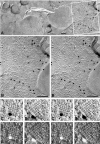

Aquaporin (AQP) water channels are abundant in the brain and spinal cord, where AQP1 and AQP4 are believed to play major roles in water metabolism and osmoregulation. Immunocytochemical analysis of the brain recently revealed that AQP4 has a highly polarized distribution, with marked expression in astrocyte end-feet that surround capillaries and form the glia limitans; however, the structural organization of AQP4 has remained unknown. In freeze-fracture replicas, astrocyte end-feet contain abundant square arrays of intramembrane particles that parallel the distribution of AQP4. To determine whether astrocyte and ependymocyte square arrays contain AQP4, we employed immunogold labeling of SDS-washed freeze-fracture replicas and stereoscopic confirmation of tissue binding. Antibodies to AQP4 directly labeled approximately 33% of square arrays in astrocyte and ependymocyte plasma membranes in rat brain and spinal cord. Overall, 84% of labels were present beneath square arrays; 11% were beneath particle clusters that resembled square arrays that had been altered during fixation or cleaving; and 5% were beneath the much larger areas of glial plasma membrane that were devoid of square arrays. Based on this evidence that AQP4 is concentrated in glial square arrays, freeze-fracture methods may now provide biophysical insights regarding neuropathological states in which abnormal fluid shifts are accompanied by alterations in the aggregation state or the molecular architecture of square arrays.